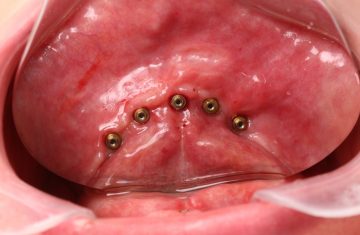

Cirurgia Guiada por Dr. João Marcelo Arcoverde

Adepto à filosofia de trabalho de que menos é mais, Dr. João Marcelo Arcoverde se tornou pioneiro no Brasil ao unir a técnica que permite repor dentes perdidos sem a necessidade de cortes e uso de bisturi convencional que diminuem drasticamente a necessidade de enxertos ósseos.

A Cirurgia Guiada é uma técnica inovadora, cujo implante dentário é feito sem cortes e pontos, portanto gerando maior conforto ao paciente, seja na reposição de um dente, de vários ou de todos.